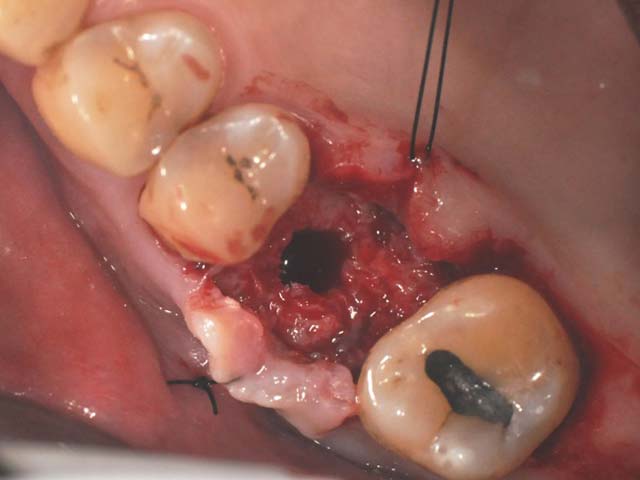

鼻竇增高術(垂直)+植牙 首頁 案例分享 人工植牙 鼻竇增高術(垂直)+植牙 鼻竇增高術(垂直)+植牙 術前評估 PRF(使用法國離心機,萃取出有益於傷口癒合的血小板,並加以濃縮) 鼻竇增高術 從植牙傷口置入萃取的PRF,將鼻竇往上抬升,再植入骨粉,以利植牙。 電腦斷層—術前,術中,假牙完成